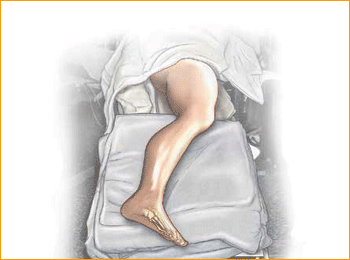

Jones Fracture Technique for 4.5 mm and 5.5 mm Headless Compression screws.

1. PATIENT POSITIONING

Position the patient in a semi-lateral position utilizing a bean bag body positioner. The patient should be moved to the distal end of the bed and the operative leg draped free as the side up. Exertion of the operative limb should be checked prior to prep and drape to confirm that

the operative limb can be positioned on the mini c-arm during surgery.